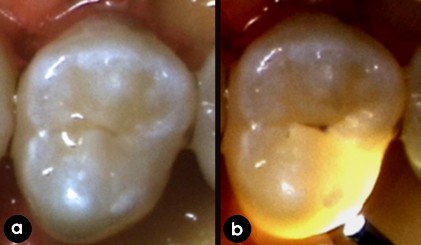

Hình 1.5: Hình ảnh FOTI trên răng:

(a) nhìn bằng mắt thường, (b) hình ảnh với FOTI [50].